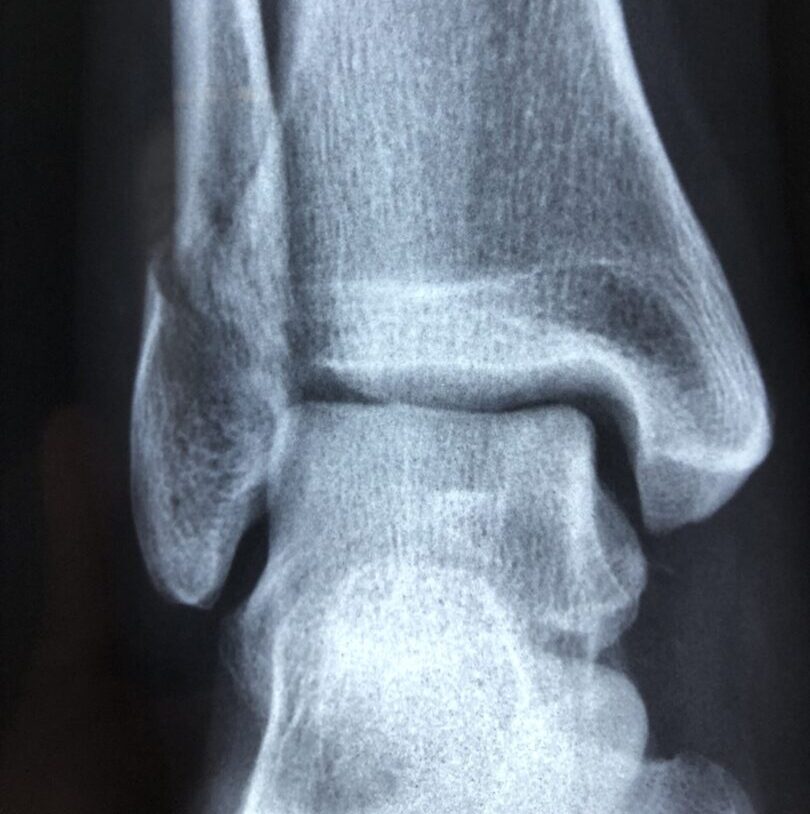

The service supports residents with a suspected fracture to an upper or lower limb (shoulder to hand, knee to foot), or where a chest X-ray is clinically indicated – in situations where the resident would previously have been taken to hospital for imaging. It is intended for residents who are clinically stable, where there is no immediate need for emergency intervention and where it is safe and appropriate for assessment to take place within the care home setting following discussion with FNC+Plus.